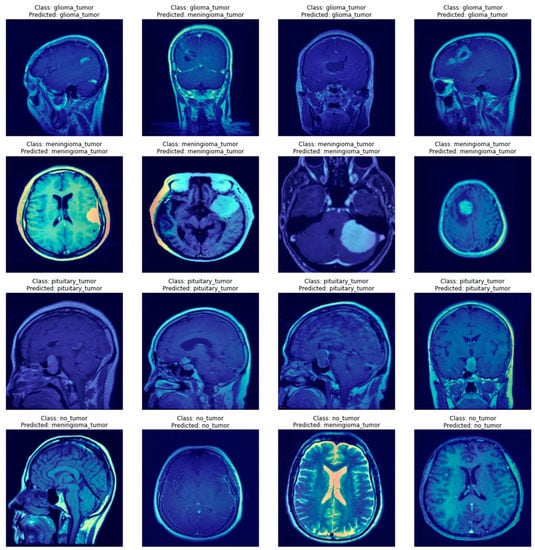

In the case of this research, explaining the decisions of neural networks is even more important than the raw scores the models achieved. It not only provides insights that allow us to assess whether the network truly learned how to solve the task but also emphasizes areas of the image important to the diagnosis. Figure 6 and Figure 7 present a few visualizations of classifications for simple versions of both types of architectures. The Grad-CAM for the CNN and Attention Rollout for the ViT were used to create the visualizations.

As can be seen in Figure 6 and Figure 7, both types of networks produced reasonable heatmaps, although in some cases, it is hard to say what made the network predict a specific class. Both architectures had problems marking up reasons for a pituitary tumor prediction, but in other cases, they were able to tag some interesting features, especially in the case of a meningioma tumor, with neoplastic changes clearly outlined from the background. Additionally, both methods do not mark anything specific in the case of no-tumor pictures, thus avoiding unnecessary noise that might distract the doctor examining scans.

The results of both algorithms are of comparable quality as they both mark similar features of the image. Still, one has to notice that the outputs of ViT’s visualizations are of better resolution, which is caused by the way the Attention Rollout casts the matrices weights by all the linearly scaling matrices of encoders, thus producing the outputs shaped similar to the network’s input. In contrast, the Grad-CAM produces a heatmap of the resolution of a chosen feature map’s dimensionality, which might differ between networks, and, in some cases, not provide satisfying outcomes. Such an example might be the Xception model, where the last convolutional layer produces feature maps of the 5 × 5 size, which does not provide any valuable insights. Furthermore, the ViT model’s visualizations show that it might be better in ignoring the background, which causes the output images to look less noisy.

It is noteworthy that these visualizations are only one of the many possible. There are different visualization algorithms, and they can be combined to achieve superior results. In addition, the output images shown in Figure 6 and Figure 7 are class-specific, which means that for every one of these images, a few more visualizations might be created, which would allow for checking whether anything was omitted while making a diagnosis.

Figure 7. A few examples of Attention Rollout produces heatmaps for the simple ViT’s decisions.

Applsci 12 11880 g007